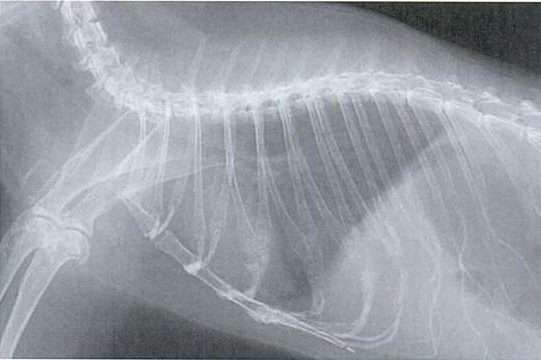

Slike dišnih puteva bez oboljenja:

Dijagnoza

Nedostatak tipičnih simptoma često otežava ranu dijagnozu. U slučaju bolesti se provode kliničke pretrage kao slušanje, mjerenje temperature, pulsa i promatranje frekvencije disanja. RTG pregled je koristan u slučaju dileme. Može pokazati da li i u kojem obimu postoje sjene u predjelu pluća. Kako se uzročnik ne može razlikovati, trebalo bi dati sekret iz nosa ili očiju, ili bris grla tj. nosa na pretrage kako bi se ustanovila kultura uzročnika i napravi antibiogram. U slučaju smrti, naročito ako je više životinja zaraženo, obdukcija bi imala smisla.